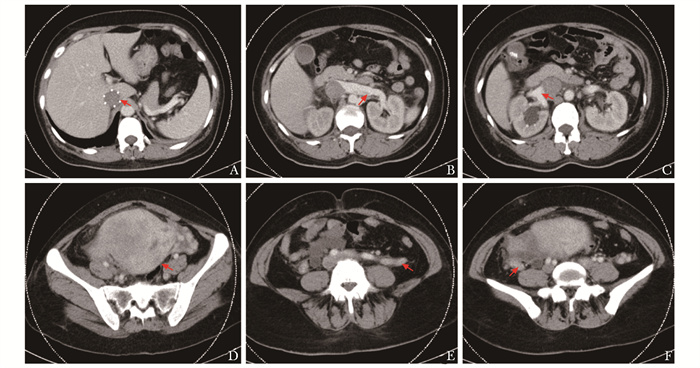

• 摘要: 低级别子宫内膜间质肉瘤(low-grade endometrial stromal sarcoma, LG-ESS)是一种罕见的子宫恶性肿瘤, 在所有子宫恶性肿瘤中占比不足1%, 目前国内外尚无关于LG-ESS导致急性完全性下腔静脉阻塞的报道。2020年11月, 北京协和医院血管外科接诊1例LG-ESS患者, 临床表现为月经紊乱、右下肢凹陷性水肿、突发恶心、少尿、肌酐升高, 影像学提示下腔静脉完全性阻塞, 通过多学科协作共同决策, 采用分期手术联合内分泌治疗成功救治该患者, 其诊疗过程体现了多学科协作在疑难重症患者诊治中的重要作用。

Abstract: Low-grade endometrial stromal sarcoma (LG-ESS) is a rare uterine malignancy, accounting for less than 1% of all uterine malignancies. And there is no literature reporting about acute obstruction of inferior vena cava (IVC) caused by LG-ESS. In November 2021, A patient diagnosed with LG-ESS was admitted to our hospital, presenting with pitting edema of the right lower limb, menstrual disturbance, nausea, oliguria andincreased serum creatinine. Imaging suggested complete obstruction of IVC cava. This difficult case was successfully treated with staging surgery combined with endocrine therapy by a cooperative multidisciplinary team (MDT). The important role of MDT in the treatment process of such a difficult and serious case was demonstrated.